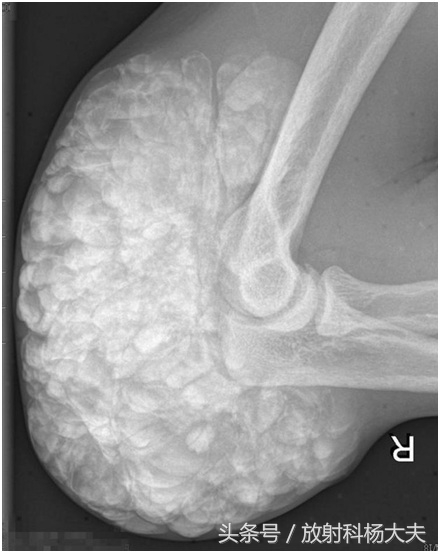

刘叔今年50岁,刘叔是赫赫有名的农村致富能手。12年前发现右侧肘部及前臂皮下多个质软结节,无明显红热痒痛现象,肘关节活动正常,随时间推移,上述结节逐渐增大,后沿尺骨方向逐渐形成成块并影响肘关节活动。刘叔半个月前来我院就诊。骨科专科检查:包块长度约10cm,宽度5.5cm,触之硬韧,边界不清,并轻微压痛。x线片:右肘关节各构成骨未见增生、破坏等骨质异常X线征,右肘关节旁软组织中可见团状阴影,团块由大量大小不一结节状高密影融合而成的。

X线检查是诊断TC的基本方法, 其表现为关节旁关节伸侧软组织中, 呈大小不一的钙化结节集结而成的分叶状团块,呈“卵石样”,“桑葚状”,范围较广者可呈“流注状”;病变一般不累及邻近关节或骨骼。CT与X线平片表现一致,但CT对病变部位、形态及范围的显示更为全面, 能清楚显示病变与邻近关节及骨骼的关系。MRI具有多参数、多序列、多方位成像的功能,可根据信号判断组织成分,。能多方位显示病变不累及关节或骨骼, 对诊断有较大帮助。